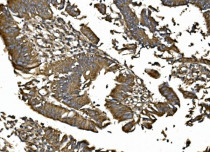

ARG43141 anti-CISD1 / mitoNEET antibody IHC-P image

Immunohistochemistry: Paraffin-embedded Human rectal cancer tissue. Antigen Retrieval: Heat mediation was performed in EDTA buffer (pH 8.0). The tissue section was blocked with 10% goat serum. The tissue section was then stained with ARG43141 anti-CISD1 / mitoNEET antibody at 2 µg/ml dilution, overnight at 4°C.